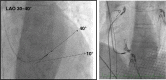

Conduction system pacing (CSP) has emerged as a more physiological alternative to right ventricular pacing and is also being used in selected cases for cardiac resynchronization therapy. His bundle pacing was first introduced over two decades ago and its use has risen over the last five years with the advent of tools which have facilitated implantation. Left bundle branch area pacing is more recent but its adoption is growing fast due to a wider target area and excellent electrical parameters. Nevertheless, as with any intervention, proper technique is a prerequisite for safe and effective delivery of therapy. This document aims to standardize the procedure and to provide a framework for physicians who wish to start CSP implantation, or who wish to improve their technique.